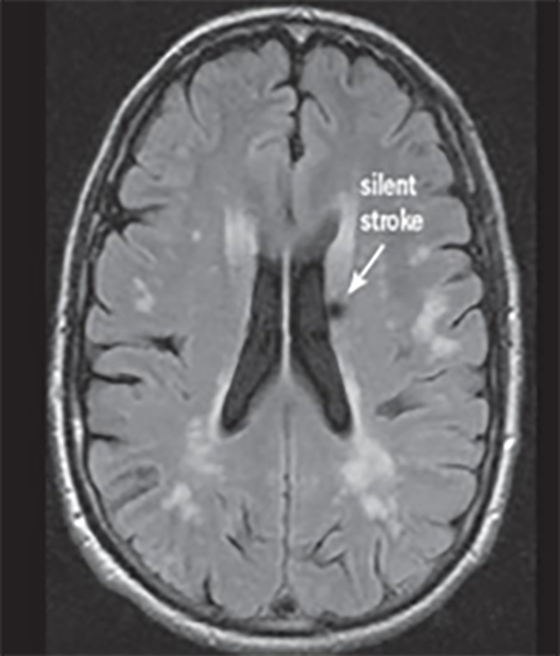

Deși unele tipuri de infarct sunt aparente pentru ochiul liber neprofesionist (Fig.2), altele sunt mai subtile și mult mai reduse în intensitatea aparentă și dimensiune (Fig.3 & Fig.4).

În imaginile din figurile 2-4 se pot vedea cu ochiul liber abnormalitățile la nivelul creierului din imaginile RMN. Astfel de cazuri reprezintă o parte importantă din setul de date, iar restul imaginilor e compus din cazuri mult mai greu de identificat sau clasificat chiar și pentru radiologii cu experiență. Pentru moment suntem departe de a concura cu precizia și acuratețea radiologilor, dar soluțiile de detecție automată de astfel de leziuni vor să vină în ajutorul medicilor. Un medic radiolog interpreta în jur de 679 imagini de tip RMN per zi în anul 2010 [9]. De atunci cantitatea de imagini produse de aparatura medicală e în continuă creștere iar presiunea asupra radiologilor crește și ea, iar cu aceasta cresc și șansele de eroare sau de ratare a unor leziuni importante. O soluție automată vine ca un adjuvant pentru radiolog asigurându-se că acestuia nu îi scapă niciun caz clar de leziune, iar radiologul se poate axa pe cazurile cu adevărat dificile și importante. Și în plus, un algoritm nu suferă de oboseală și nici nu necesită repaus.

Fig. 4 SImulare de detecție infarct cerebral din RMN-DWI. Ref: [8]